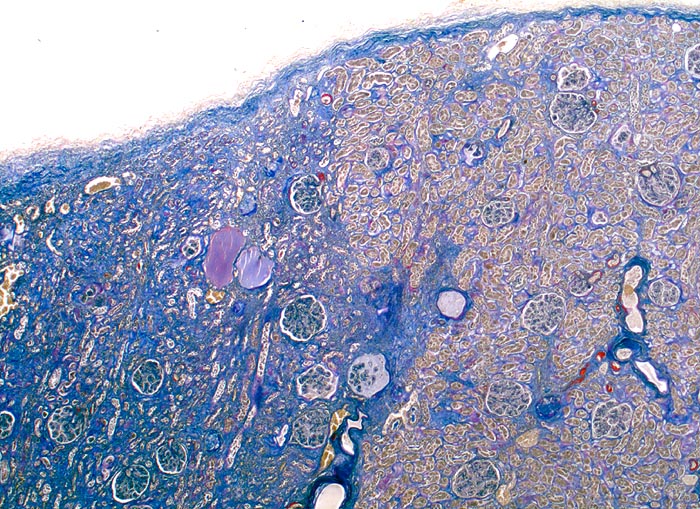

PathoPic – image database / PathoPic ID 4643 - Subinfarkt

Subinfarkt

Niere

In der linken Bildhälfte ischämisch bedingter Subinfarkt der Niere mit fokaler tubulärer Atrophie und interstitieller Fibrose. Aufgrund der tubulären Atrophie stehen die Glomerula etwas dichter zusammen. Schon in der Übersicht ist die schwere Arteriolosklerose erkennbar.

Als Folge stenosierender Gefässveränderungen kommt es zu fokaler ischämischer Atrophie der Nierenrinde (Subinfarkt) gekennzeichnet durch eine tubuläre Atrophie und interstitielle Fibrose.

Diabetes mellitus Typ II und arterielle Hypertonie seit 10 Jahren. Leichte Proteinurie.